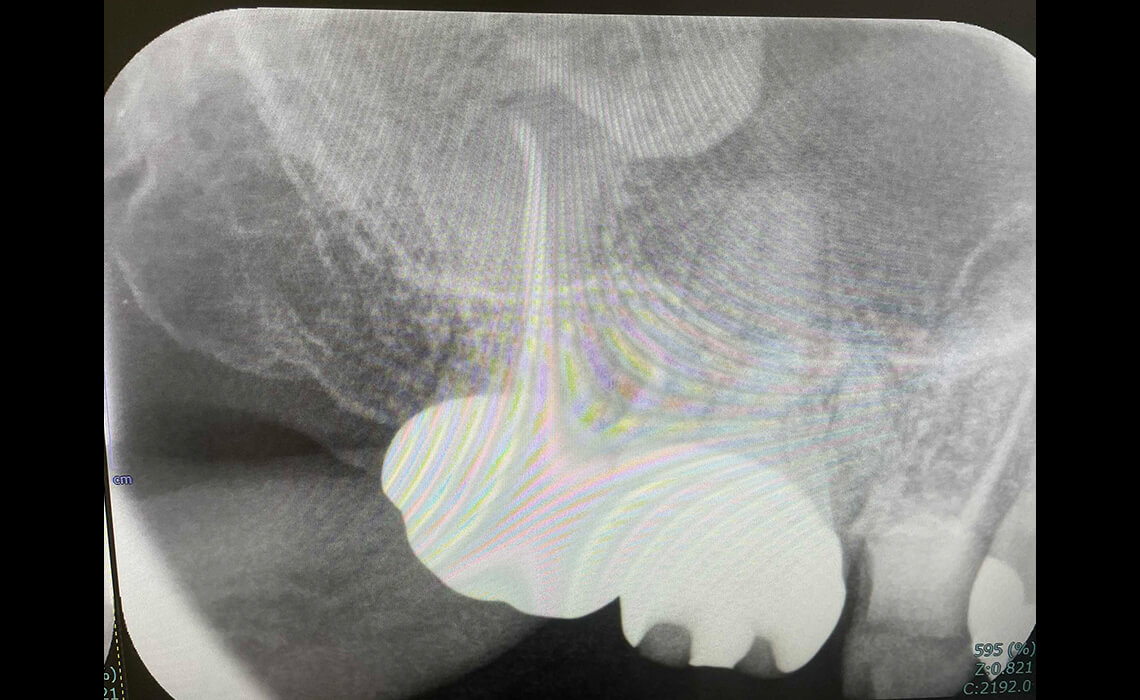

根管治療の最後の仕上げとして「根管充填」というものがあり、これは、歯の神経を取ったことにより空洞になった根管内を、緊密に塞ぐことを指します。

この隙間を塞ぐことができなければ、これが原因となり数年が経過した時に再び感染してしまうことがあります。一般的には「ガッタパーチャ」と呼ばれる、ゴムのようなもので隙間を塞ぐのですが、根管内は複雑な構造になっていますので、隙間を残してしまうことがあるため、再治療を行うケースが多いのです。

それに対して、「MTAセメント」と呼ばれるものは隙間を塞ぐことができ、かつ、殺菌作用及び強い接着性、歯の組織を再生させる効果があるため、治療後の経過が非常に良好になります。当院では、根管の高い封鎖性、適合性、歯と一体になる再石灰化性を持つMTA系セメントを使用しています。

感染が取り除けたら、MTAセメントやガッタパーチャを用いて根管を緊密に封鎖します。MTAセメントは高い封鎖性と生体親和性を持ち、歯の保存性をさらに高めます。